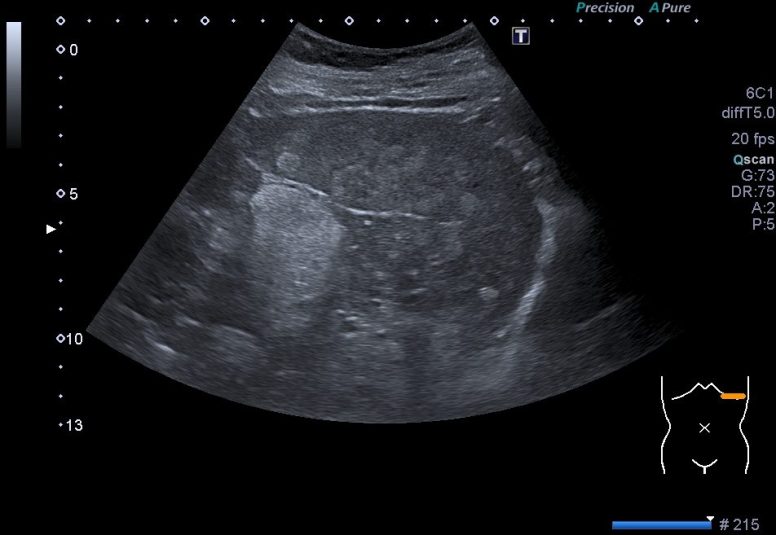

Toca ahora ver las imágenes patológicas:

Observas, semiólogicamente hablando, un bazo con una gran cantidad de lesiones ocupantes de espacio, hiperecogénicas que afectan a toda la ecoestructura. Doppler normal.

La Sarcoidosis o enfermedad de Besnier-Boeck es una enfermedad que afecta raramente de forma exclusiva al Bazo. Es una enfermedad granulomatosa no caseificante, en otras palabras, es una patología que masas mas o menos esféricas de células que proliferan cuando el sistema inmunitario detecta una amenaza (granulomas), y que además es una reacción de tipo autoinmune, de carácter inflamatorio, no necrótico, es decir, no implica «destrucción titular».

Este caso que te presento ya había debutado en otras localizaciones, no afectaba únicamente al bazo, una vez revisada la historia clínica de la paciente, el radiólogo me comentó que la afección era ya conocida, aunque el hecho de verlo en el bazo, era un hallazgo no filiado hasta este momento.

Compara normalidad y patología. Cuando vi este bazo me asusté, pensé que era otra cosa y avisé al radiólogo inmediatamente, saltaron mis alarmas, pero finalmente se comprobó que la sarcoidosis ya era conocida y que mi miedo era infundado. Siempre que veamos anormalidad, debemos tener en cuenta las líneas rojas, lesiones nodulares sólida ocupantes de espacio en órganos compactos del abdomen, pueden ser una de estas líneas rojas y estas deben ser comentadas siempre con el radiólogo responsable.